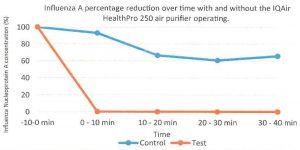

Vi har nu en frisk test, udført af laboratoriet AIRMID, der viser at IQAir HealthPro 250 er et effektivt våben imod luftbåren COVID-19 virus-smitte. IQAir HealthPro 250 reducerede i løbet af de første 10 min. antallet af virus i rummet med 99,9%, hvilket må siges at være fremragende. Testen er udført med virus A(H1N1) som har samme størrelse som COVID-19 virus. Hent certifikatet her på siden. (Nederst til højre)